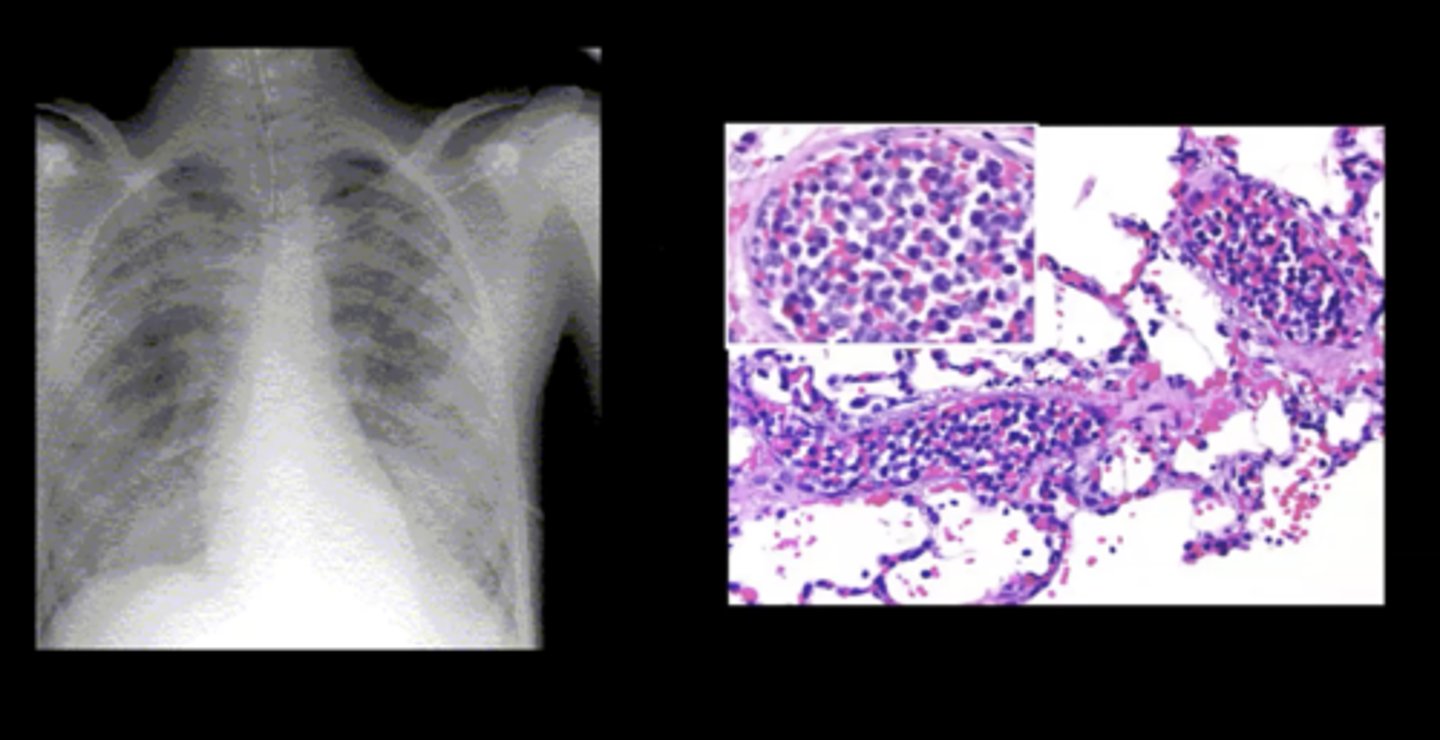

Pulmonary leukostasis

Sudden shortness of breath and progressive dyspnea; caused by a WBC clot

<p>Sudden shortness of breath and progressive dyspnea; caused by a WBC clot</p>